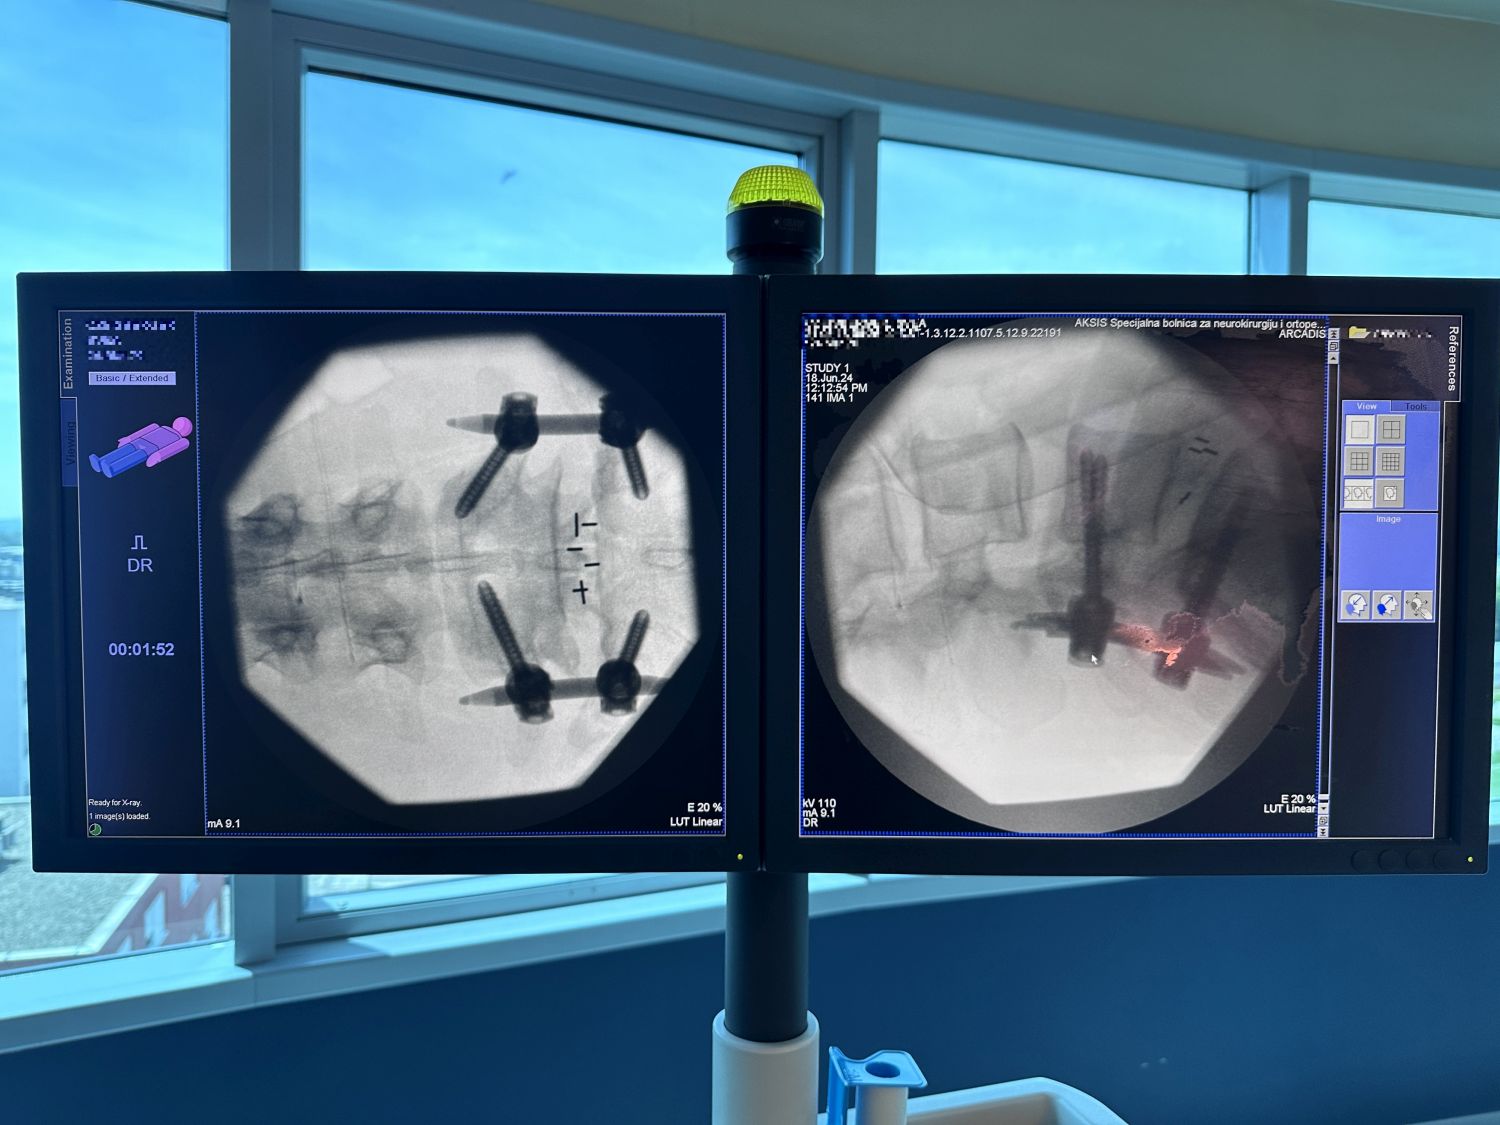

Ponosni smo na našu predanost i vrhunske rezultate u neurokirurgiji kralježnici. U zadnjih nekoliko dana naš izvanredni tim izveo je i dvije napredne i zahtjevne operacije kralježnice koje su pacijentima donijele olakšanje i poboljšanu kvalitetu života – METRx mikro-endoskopsku stražnju dekompresiju vratne kralježnice, te miniOpen TLIF spinalnu fuziju.

Naše iskustvo, znanje i tehničke mogućnosti omogućuju nam izvođenje najsloženijih zahvata s visokom stopom uspjeha. Zahvaljujući naprednoj tehnologiji i kontinuiranoj edukaciji naši neurokirurzi pružaju najbolju moguću skrb. U nastavku pogledajte slike koje prikazuju preciznost i inovativnost naših zahvata.